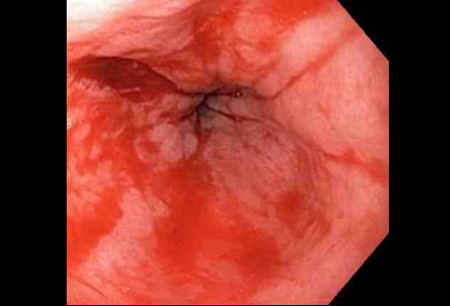

- gastroscopy